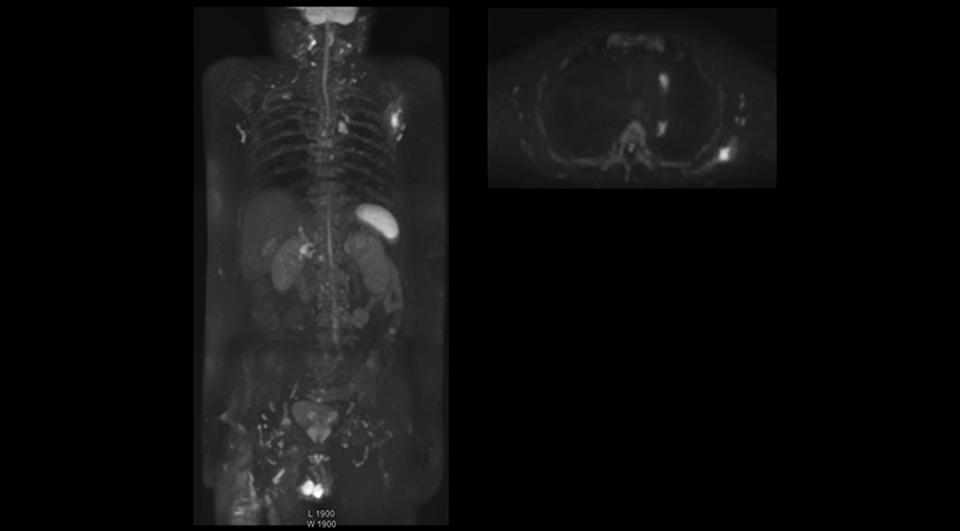

“With coronal DWIBS, we can perform a full whole body exam, including other sequences, within 30 min.”

Coronal DWIBS is faster and improves image quality

“Switching to coronal DWIBS – rather than axial – further shortens scan time,” says Mr. Naka. “Important is that a dS SENSE factor of 5 shortens exam time while high image quality can be maintained, thanks to Ingenia’s dStream architecture.” He adds that the coronal orientation also avoids artifacts that are specific to combining axial images.

“When we use a coronal DWIBS acquisition, we can perform a full whole body examination, including other required sequences, within 30 minutes,” he says.

“This is considerably faster than the previously used exam with axial whole body DWI, which took more than 45 minutes,” he notes. “A shorter exam is more patient-friendly and allows us to also use it on patients in poor health who would have difficulty tolerating a long exam. Limiting the exam time is also helpful for scheduling, because it fits in a normal single exam timeslot.”

faster whole body mri kawasaki